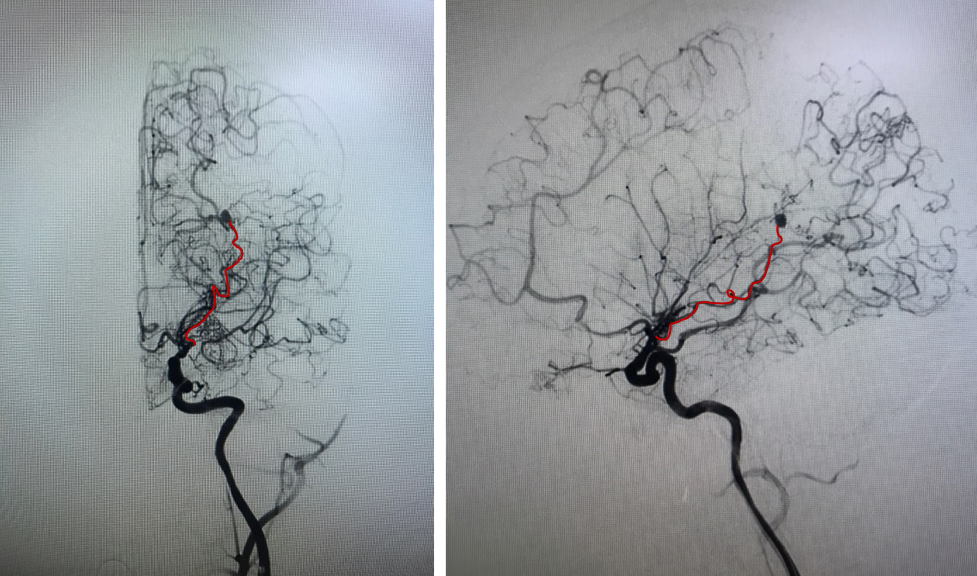

手术计划

术前诊断

烟雾病

脉络膜前动脉假性动脉瘤

手术方案A:动脉瘤栓塞联合低流量搭桥。

手术方案B:动脉瘤切除联合低流量搭桥。

有观点认为此类动脉瘤可以保守治疗,因为较小的脑室旁动脉瘤可能自发消退,但同样存在保守治疗的病例预后不佳[1-4]。深部动脉瘤通过血管内介入治疗往往能取得较好的疗效,治疗能否成功关键取决于载瘤动脉直径[5]。血管内栓塞通常是烟雾病患者脑室旁动脉瘤的首选方案,因为可以避免开颅手术对脑实质的损伤及相关的缺血事件发生[1]。在一项病例系列研究[6]中,血管内栓塞成功治疗了7例(88%)烟雾病伴脑室旁动脉瘤且无围术期并发症,其中6名患者在出院时完全康复(75%)。然而,烟雾病患者载瘤动脉往往十分迂曲,且动脉瘤容易破裂[5]因此血管内治疗往往充满挑战。显微手术夹闭是动脉瘤的传统治疗方法,但在治疗深部动脉瘤时,术中破裂的风险可能更高。微创手术如小骨窗和神经内镜已用于治疗颅内深部病变,并取得了不同程度的成功。

在本例病例中,针对脑室内动脉瘤,我们首选血管内治疗栓塞脑室旁动脉瘤,因为血管过于迂曲尝试失败。术后出现脑室内出血,于是启动备选方案,急诊在磁共振导航下通过endoport辅助进行动脉瘤切除,同时部分清除脑室内血肿并放置脑室外引流,降低远期脑脑积水的风险。随着神经内镜的普及,深部的脑血管病变的治疗方案有了更多的选择,而充分的术前评估与周全的手术方案规划是手术安全与成功的基石。